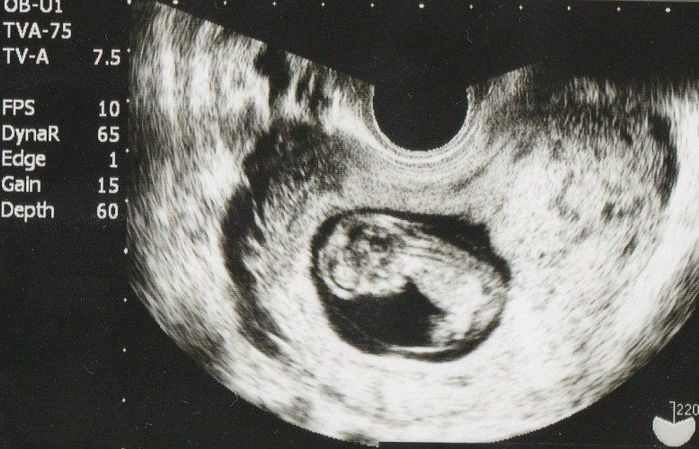

妊娠10週目のエコー写真

胎嚢のなかにすでに人間らしい形に成長している赤ちゃんを発見! 左側に頭、右下のほうが脚のようです。未発達ですが、目や脳と、うっすら白く背骨らしきものが見えます。二度目の生命誕生は、一度目とまた違った感動がありました。

上の画像の拡大です。人間らしい頭と胴体に別れ手足も写っています。ですが、大きさにしてみるとまだまだ33mm。長女は、「あかちゃん?ここ?」と私のおなかとこのエコー写真を、じーっと不思議そうに見ていたのを覚えています。